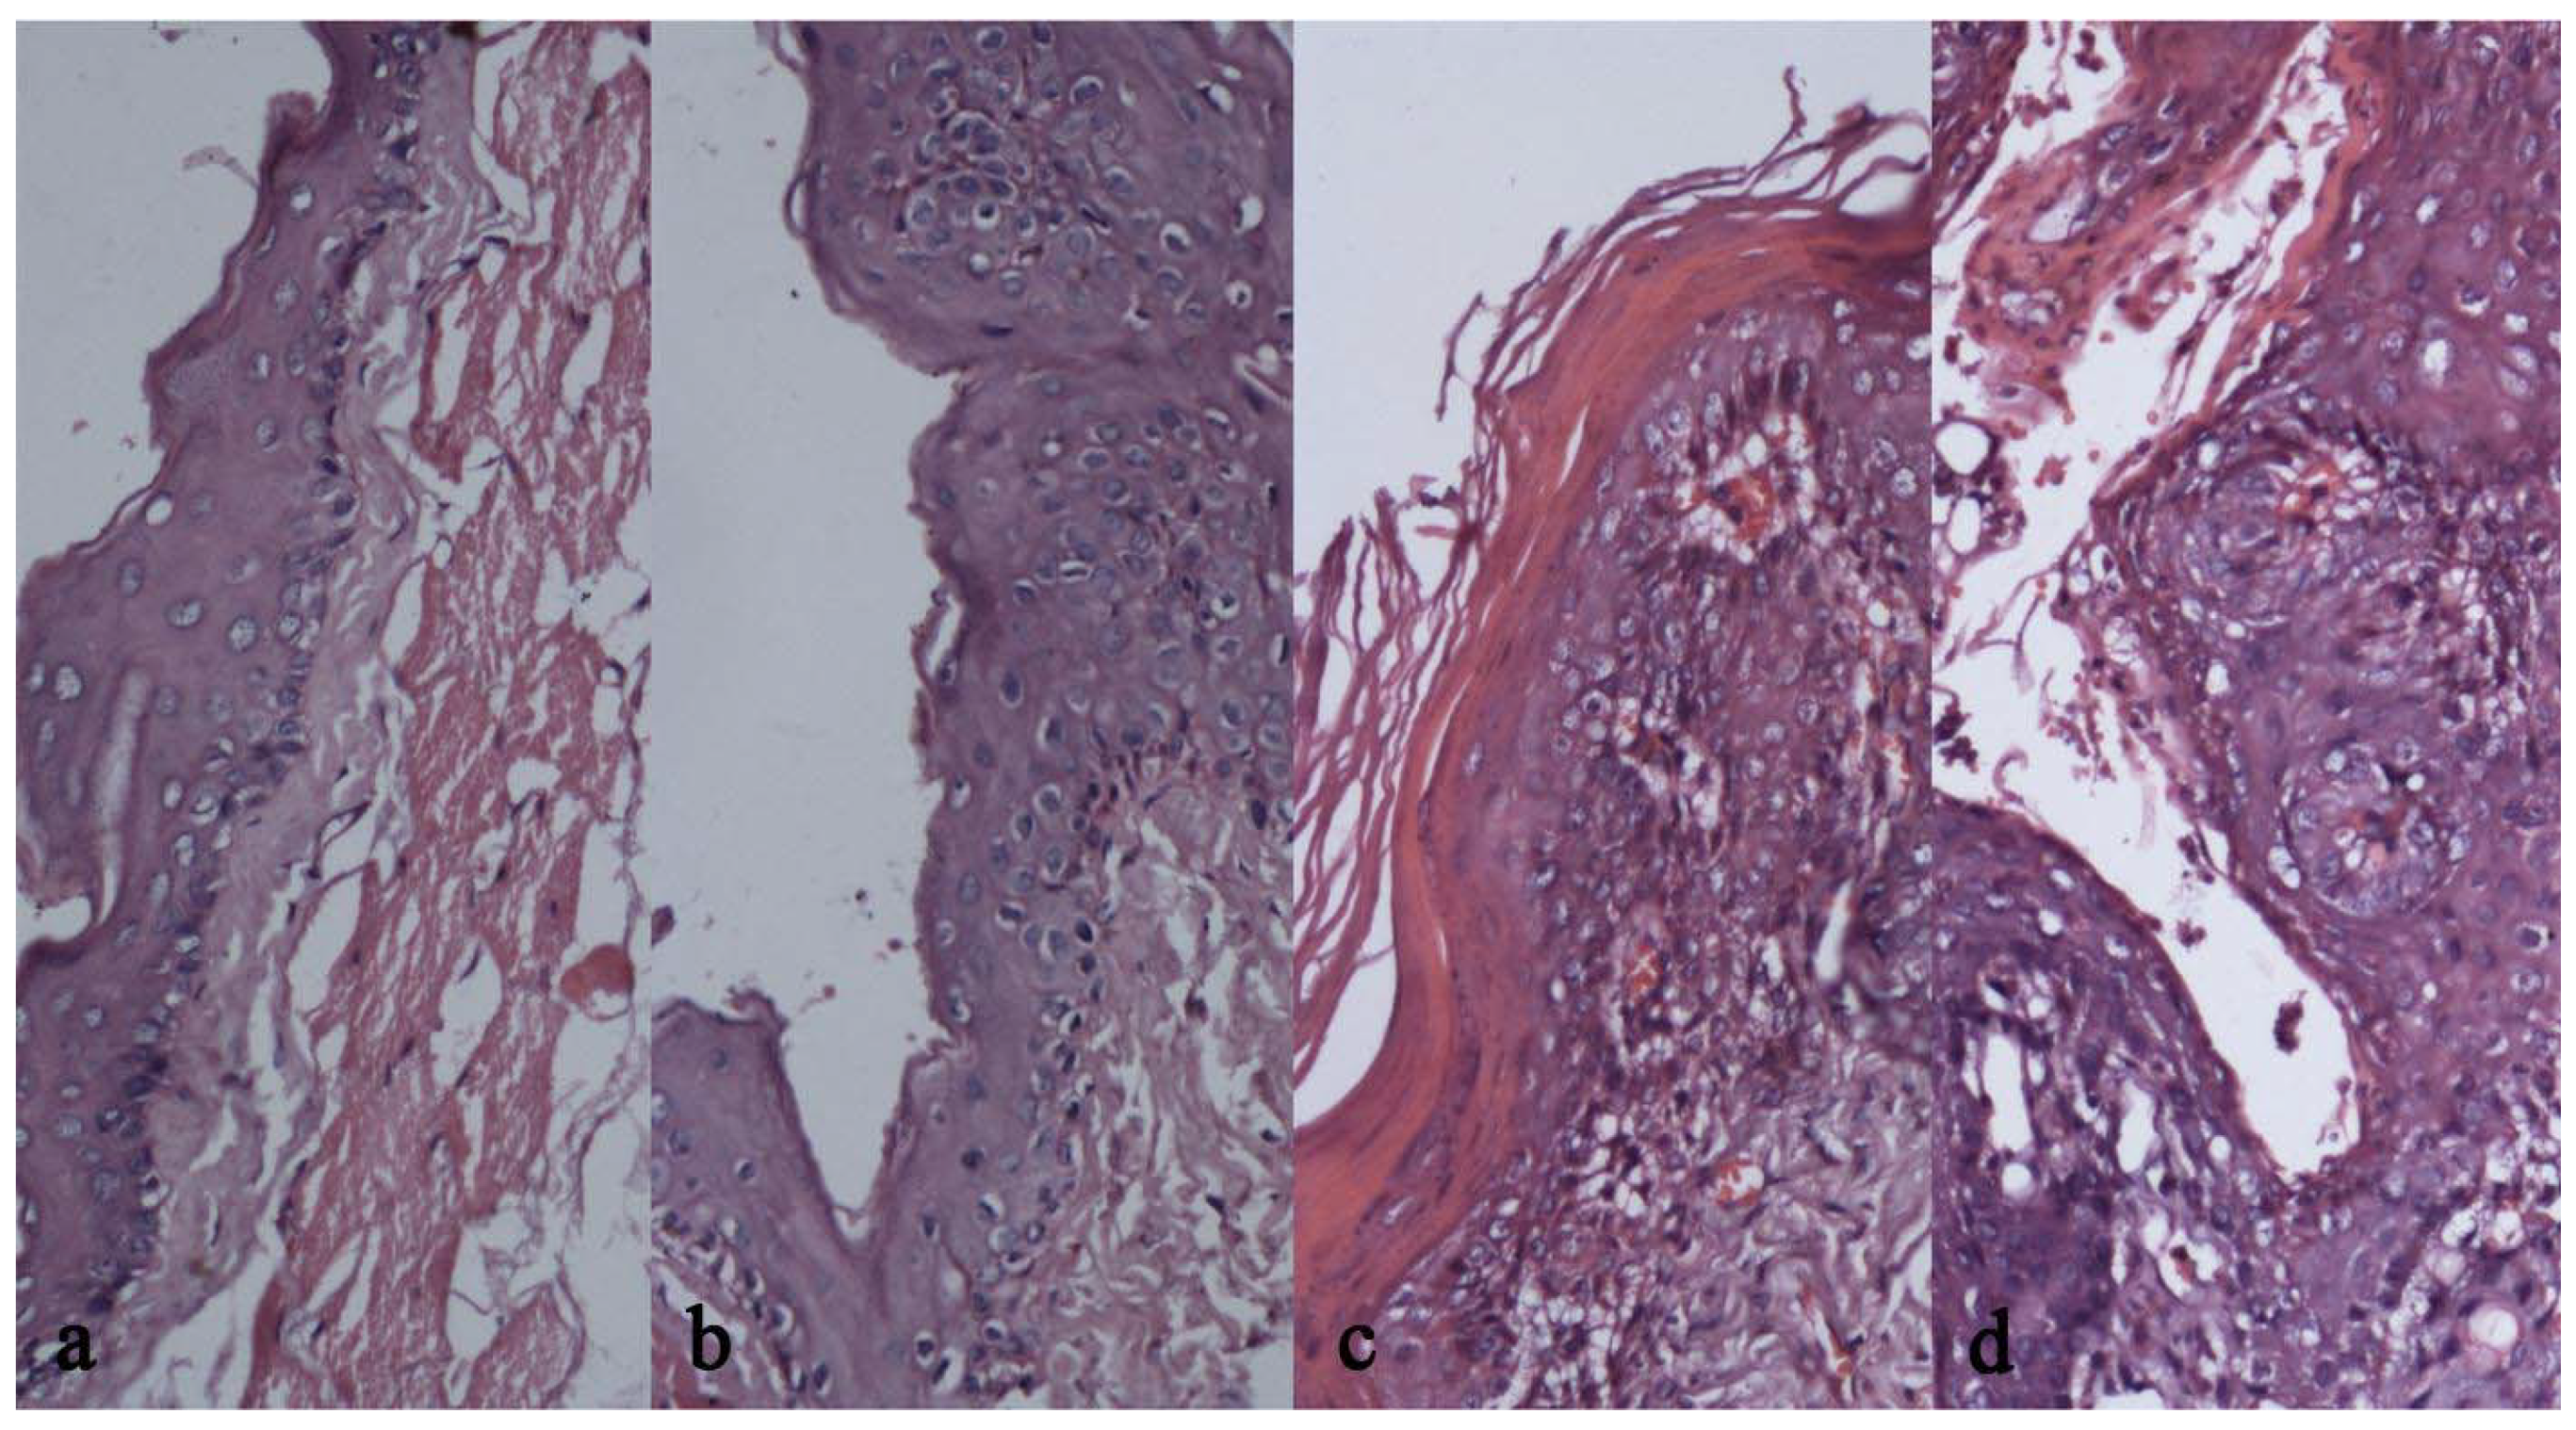

2.5. Results of Pathologic Observation

The histopathologic observations are separately presented in Table 4 and Table 5. It can be seen that treatment group had constantly larger number of normal cases than model group, P < 0.01 by the χ2 test. The treatment group had consistently smaller numbers of paraplasm than the model group, P < 0.05 by the χ2 test. Table 6 presents the incidences of different histological states, which had significant differences between the two groups by the rank-sum test (P < 0.01). Histopathologic changes were observed microscopically with HE staining (Figure 3). In the blank group, keratinized stratified squamous epithelium with regular cell arrangement, no rete pegs or no obvious rete pegs were observed, a prickle cell layer that was thinner than in normal human mucosa and the basal layer cells were obvious. Comparison of epithelial dysplasia revealed that at Week 3, compared with the treatment group, the model group had irregular epithelial layers, darker nuclei with larger nucleoli with the majority of basal layer cells losing polarity, and increased mitotic figures. At Week 6, one animal in the model group developed serious non-typical hyperplasia involving most of the epithelium that was hardly reversible. At Week 9, one animal in the control group was assessed as OSCC based on obvious cell heteromorphism, epitheliosis intruding the connective tissues in blocks or streaks, and part of the epithelium exhibiting obvious horny pearls, increased mitotic figures, and polymorphism of cells and nuclei. After Week 12, squamous cell carcinoma appeared in both model and treatment groups, but with significantly fewer animals with squamous cell carcinoma in the treatment group, and more serious mitotic phase increases in the model group. Among them, 5 animals in the treatment group had keratized epithelium, the majority had hyperkeratosis and the minority had dyskeratosis, acanthosis, basal membrane remaining regular, and infiltration of lymphocytes and plasmacytes under the proper layer. All of these animals showed general inflammatory reactions, while paraplasm or squamous cell carcinoma that was more serious than in these animals was observed in the model group.

Figure 3. (a). Tissue sections at 9 weeks in the Treatment Group; (b). Tissue sections at 9 weeks in the Model Group; (c). Tissue sections at 12 weeks in the Treatment Group; (d). Tissue sections at 12 weeks in the Model Group.